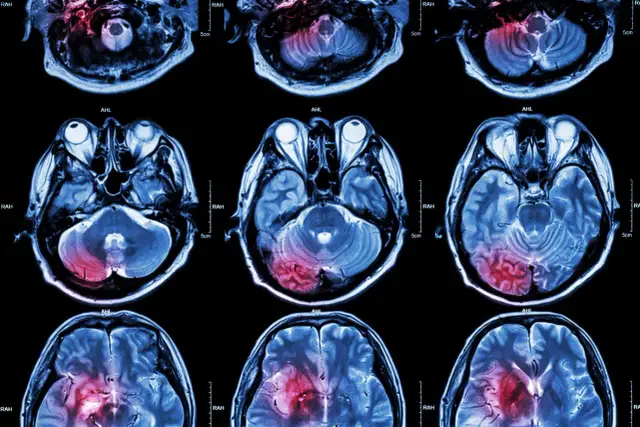

Udar mózgu: poznaj jego przyczyny, typy i czynniki ryzyka. Dowiedz się, jak styl życia wpływa na zdrowie mózgu i jak skutecznie zapobiegać.

Poznaj przyczyny udaru mózgu: niedokrwiennego i krwotocznego. Dowiedz się, co zwiększa ryzyko (styl życia, choroby) i jak skutecznie zapobiegać.

Udar: Jak stymulować mózg do regeneracji? Poznaj neuroplastyczność, skuteczne metody rehabilitacji, dietę i wsparcie. Odzyskaj sprawność!